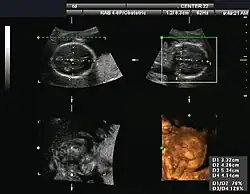

Orthogonal planes of a three-dimensional sonographic volume with transverse and coronal measurements for estimating fetal cranial volume[17][18]

Gynecologic ultrasonography examines female pelvic organs (specifically the uterus, ovaries, and fallopian tubes) as well as the bladder, adnexa, and pouch of Douglas. It uses transducers designed for approaches through the lower abdominal wall, curvilinear and sector, and specialty transducers such as transvaginal ultrasound.[19]

Obstetrical sonography was originally developed in the late 1950s and 1960s by Sir Ian Donald[20][21] and is commonly used during pregnancy to check the development and presentation of the fetus. It can be used to identify many conditions that could be potentially harmful to the mother and/or baby possibly remaining undiagnosed or with delayed diagnosis in the absence of sonography. It is currently believed that the risk of delayed diagnosis is greater than the small risk, if any, associated with undergoing an ultrasound scan. However, its use for non-medical purposes such as fetal "keepsake" videos and photos is discouraged.[22]